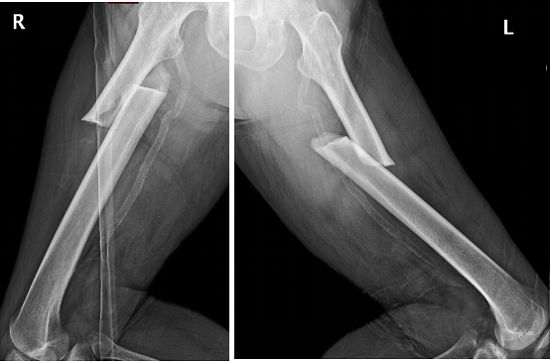

2018年上海交通大學醫學院附屬仁濟醫院創傷骨科碰到了一位從馬路臺階上摔倒的老年女性患者,拍片顯示是雙側股骨干近三分之一骨折(圖1),很對稱。

圖1

李占玉醫生團隊當時嚇了一跳,輕微暴力就能引起雙側股骨干骨折,這比較少見,肯定是病理性骨折,首先想到的是腫瘤所致,追問病史,患者否認有腫瘤病史,但有系統性紅斑狼瘡30多年,口服福善美5年,但已經停藥2年,在摔倒前有左側大腿根疼痛。根據病人的病史、體征和X線片所見,我們診斷為非典型股骨骨折,然后行髓內釘內固定術,術后8個月骨折愈合(圖2)。

圖2:髓內釘固定骨折,術后8個月,骨折愈合